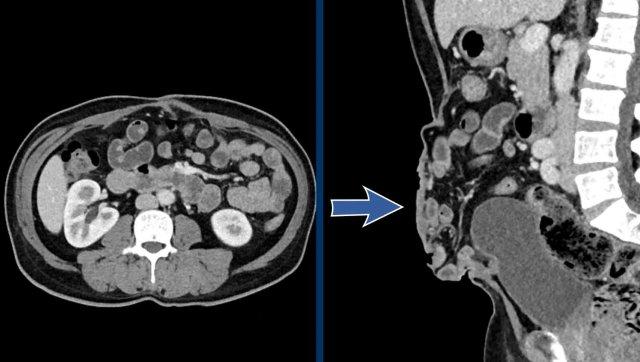

Ở bệnh nhân này với khối thoát vị lớn, các số đo như sau:

- Thể tích túi thoát vị (HSV) = (274 x 71 x 304 mm x 0,52) x 10-6 = 3,1 lít.

- Thể tích khoang bụng (ACV) = (251 x 131 x 342 mm x 0,52) x 10-6 = 5,8 lít.

- Tổng thể tích phúc mạc (TPV) = ACV + HSV = 3,1 + 5,8 = 8,9 lít.

Mức độ mất vùng chứa trong trường hợp này là thể tích túi thoát vị chia cho tổng thể tích khoang phúc mạc:

3,1 : 8,9 = 35%.

Con số này vượt xa ngưỡng 20% và có nghĩa là nguy cơ biến chứng trong và sau phẫu thuật tái tạo thành bụng đơn thuần là rất cao.